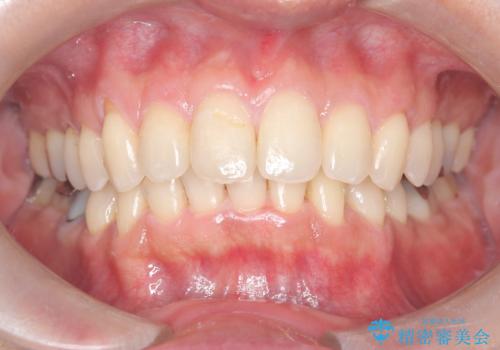

- 50代の患者様で、右上の八重歯と歯並びの乱れを気にされてご来院されました。特に、すでに装着されている前歯のセラミックブリッジを外したくないという強いご希望がありました。精密な検査の結果、八重歯を治すためのスペースが不足しているため、右上の4番目の歯(小臼歯)を抜歯し、そのスペースを利用して歯並び全体を整える治療計画を立案。装置には目立たないインビザラインを採用し、ブリッジを温存しながら八重歯の改善を目指しました。

今回の治療で最も重要だったのは、患者様のご要望通り既存のセラミックブリッジを外さずに矯正を進める点でした。計画通り右上の小臼歯を抜歯し、透明なインビザラインを使用して抜歯スペースを閉じながら、八重歯を正しい位置へ移動させました。ブリッジの形態と調和するに、他の歯の移動を工夫をすることで、複雑な条件をクリア。治療の結果、長年気にされていた八重歯が解消され、見た目が大きく改善しました。50代からでも、ご自身の要望を叶えながら、美しく機能的な歯並びを獲得していただけました。